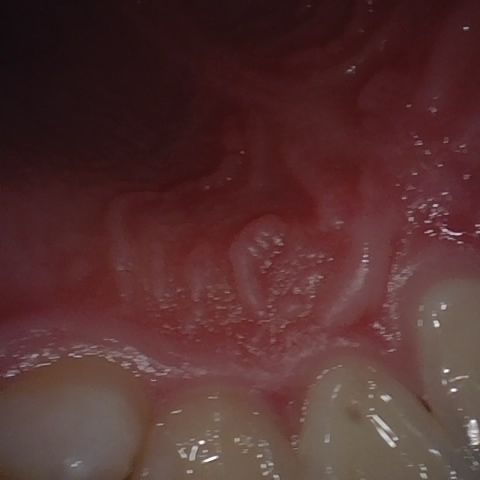

Annotated as "Good"